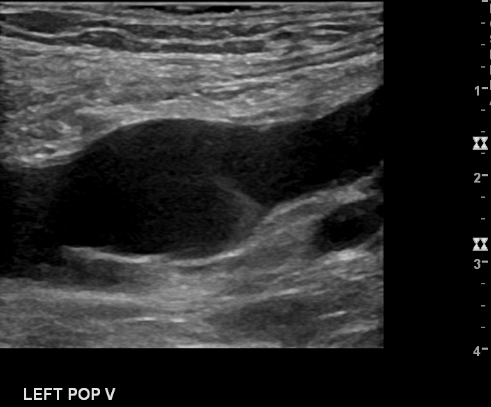

A popliteal vein aneurysm is a dilatation of the popliteal vein. It is uncommon. A busy vascular medicine specialist may see about one a year. Although over 100 cases have been published it is not really clear what to do for patients with a popliteal vein aneurysm. The most dangerous reported problem with this finding is lethal pulmonary embolism. This can occur even despite anticoagulation.

Popliteal vein aneurysms are not common. They occur much less frequently than arterial aneurysms. Only case reports and case series exist to guide us with management. Many of the cases that have been published were of pulmonary emboli complicating these aneurysms. But this does not mean that the incidence of embolism is high. In other words, maybe many aneurysms exist without causing complications and so we just don’t know about them. One thing is probably correct though. With popliteal vein aneurysms size and shape matter. First, the bigger they are the more clots form in them. The ‘magic number’ is 20 mm. If they are bigger than 20 mm the probability for thrombus rises. The second issue is shape. Saccular aneurysms are more dangerous than fusiform ones. Saccular aneurysms are ‘berry’ like projections from the main vein. A fusiform aneurysm is when the whole vein widens.

If surgery is not chosen, popliteal vein aneurysms need to be followed. The most convenient way to do so is with serial duplex. There are no guidelines as to the frequency of surveillance. There are also no guidelines other than size to make one know when something is going wrong.